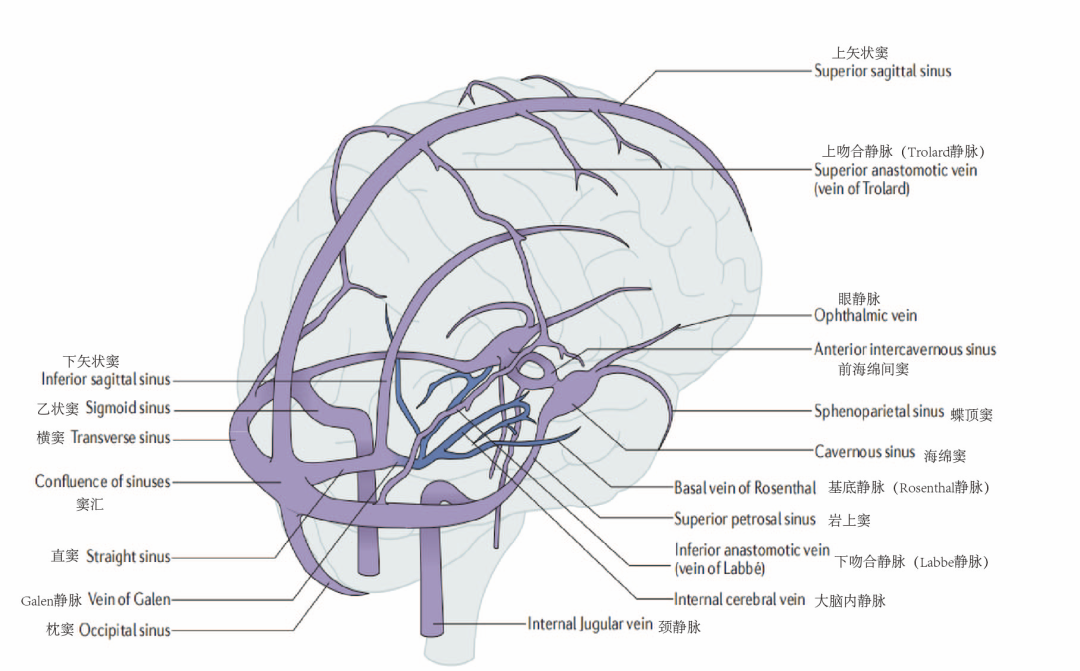

在看过患者影像学报告后告诉我们,刘同学所患脑梗的特殊之处在于,它并不是由于大脑动脉的梗塞,而是静脉脑梗。

图3. 脑静脉系统解剖示意图。蓝色血管代表深静脉系统。

当静脉堵塞时,动脉血依然可以源源不断地给大脑供给,但是无法很好地回流到心脏了,血液只进不出、瘀滞在大脑里面,从而出现脑水肿,甚至血管爆炸、危及生命。